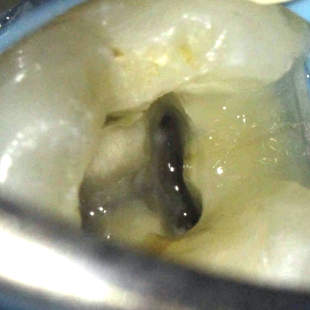

The importance of magnification and light cannot be emphasised enough when treating teeth with complex morphology.

The anatomy of the pulp floor is darker in colour. These dark dentine lines provide a helpful ‘map’ to guide the clinician to where the canal orifices are located. A long, sharp endodontic probe (DG16) can then be used to scout the entrance of the canals.

The access cavity will need extending in the direction of the extra canal (RE: disto-lingual or RP: mesio-buccal). A blunt-ended bur (such as an Endo-Z bur) is very useful to enlarge the access as required. Ultrasonics also provide a controlled and conservative way of refining the shape of the access cavity to allow straight line access.

Use fine ultrasonics to conservatively open the isthmus to search for this canal (Figure 7).